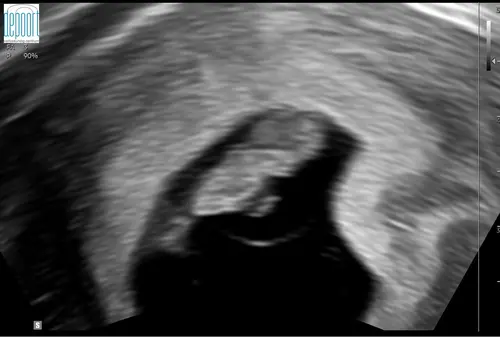

Vandaag een herhaal vitaliteitsecho gehad. Omdat ik 2 weken terug al 7+2 weken dacht te zijn bij de eerste vitaliteitsecho, maar werd teruggezet naar 6+2 weken. Voor mijn eigen gemoedsrust kreeg ik vandaag nog een herhaling. Nu bleek ik toch bijna 9 weken te zijn. Super blij en opgelucht. 🫶🏼🩵🩷